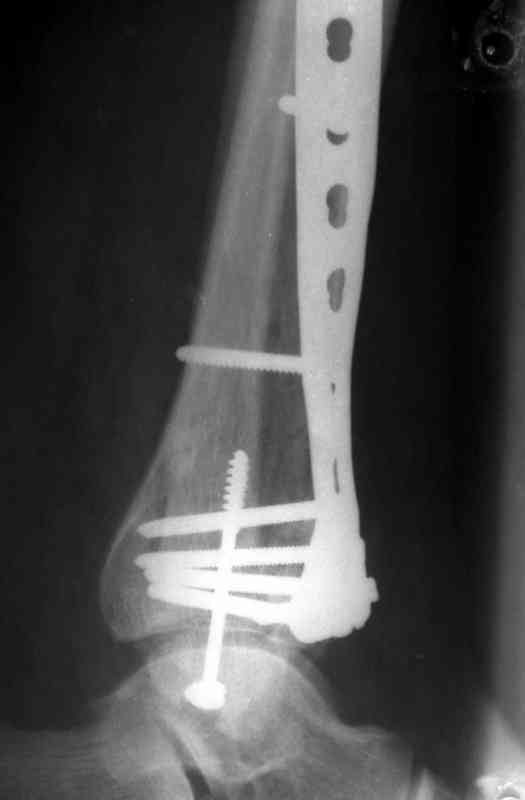

Это типичный перелом пилона, который надп лечить только открыто.Извини те что опоздал к обсуждению, но даже если вы уже оперировали больного по Илизарову это даже лучше.Посылаю картинки.

Посмотрим вроде прошло если понравится напишите расскажу как это сделать.По принципам АО кстати при поступлении сначала восстанавливают длину малоберцовой кости фиксируют пластиной 1/3 трубки потом накладывают аппарат наружной фиксации и через 7-10 дней открыто восстанавливают большеберцовую кость.С уважением Дрягин

На рентгенограммах типичный перелом пилона по типу С-3. есть опыт до 100 открытых опреаций у нас в клинике. 20 примерно в год. Принцип один -все внутрисуставные переломы нуждаются в открытой репозиции и внутренней стабильной фиксации. При поступлении КТ не надо, так как получается только нагромождение костей. Истинной картины нет. Главное восстановить длину малоберцовой кости - это ключ к успеху. При поступлении меньше всего надо думать о сосудистых расстройствах, т.к. сама операция и репозиция даже сначала частичная даёт улучшение сосудитых нарушений. Причём очень быстро. Операция в 2этапа. При поступлении доступ позади наружной лодыжки, причём обязательно. После этого репозиция малоберцовой кости и фиксация пластиной 1/3 трубки под винт 3,5. Дренаж и любой аппарат наружной фиксации. Затем после спадения отёка на 5-7-10 день аппрат снимается и дугообразный разрез спереди от медиальной лодыжки 10-12 см. Главной чтобы расстояние между 1 и вторым разрезом было не меньше 7-8 см. Тогда не будет некрозов лоскутов. Таранная кость используется как матрица на неё укладываются отломки и фиксируются пицами. Ренг-контроль. Отломки лежат все отдельно, но ничего не высыпется. При переломах С-3 всегда нужна костная пластика (из крыла). Фиксация пластиной лист клевера простой или LCP. Гипс не нужен. Дренаж до 48 часов. Операция длится 3-4 часа обязательно без жгута. Посылаю примерно такой же случай.

Посылаю результат лечения предыдущего больного через год.